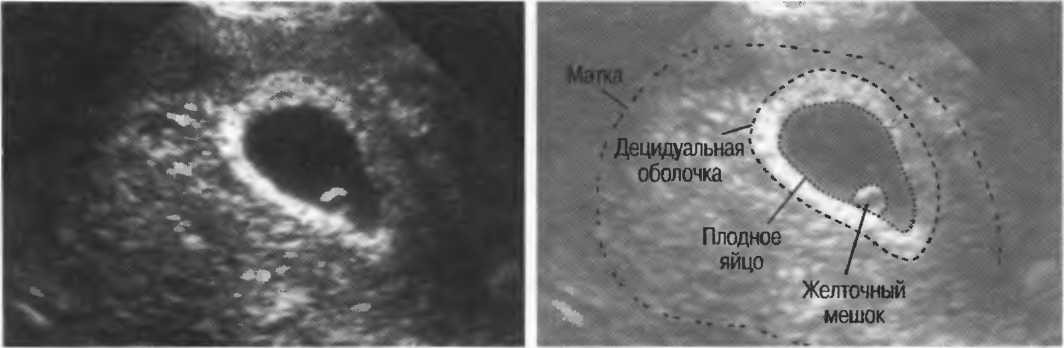

Рис. 12. Фокусировка правильна слева, так как визуализируются детали желточного мешка. Справа детали не видны, так как фокусное расстояние значительно больше.